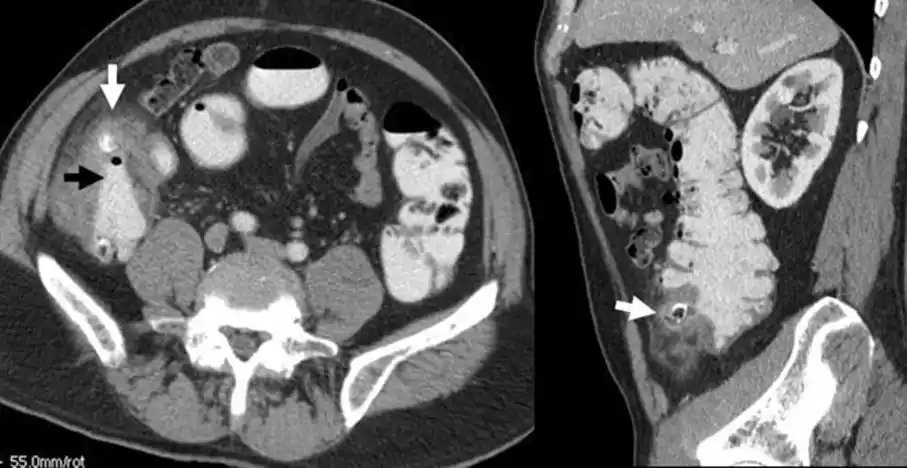

结肠憩室炎的ct真相:专家解读不寻常表现